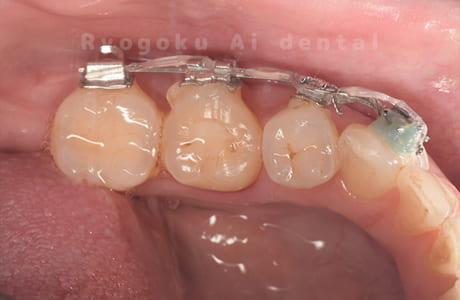

Case27

-

重度カリエス

歯牙移植咬合面術前 -

移植する親知らず

歯牙移植術直後咬合面

歯牙移植術後咬合面

歯牙移植術前側面

歯牙移植術中側面

歯牙移植術後側面

部分矯正術前咬合面

部分矯正術中咬合面

部分矯正術後咬合面

部分矯正術前側面

部分矯正術中側面

部分矯正術後側面

- 原因

- 重度カリエス

- 治療内容

- 自家歯牙移植、部分矯正

- 治療費用

- 220,000円(移植費用)

110,000円(部分矯正費用)

虫歯が大きく、保存不可能となった歯を上の親知らずと交換する自家歯牙移植を行いました。移植歯が小ぶりであったため、部分矯正を行い問題なく噛み合い、経過良好です。

<リスク・副作用>

治療後、痛みや違和感、出血、腫れなどが出る事があります。喫煙者、糖尿病などの方の場合、歯が生着しない場合があります。